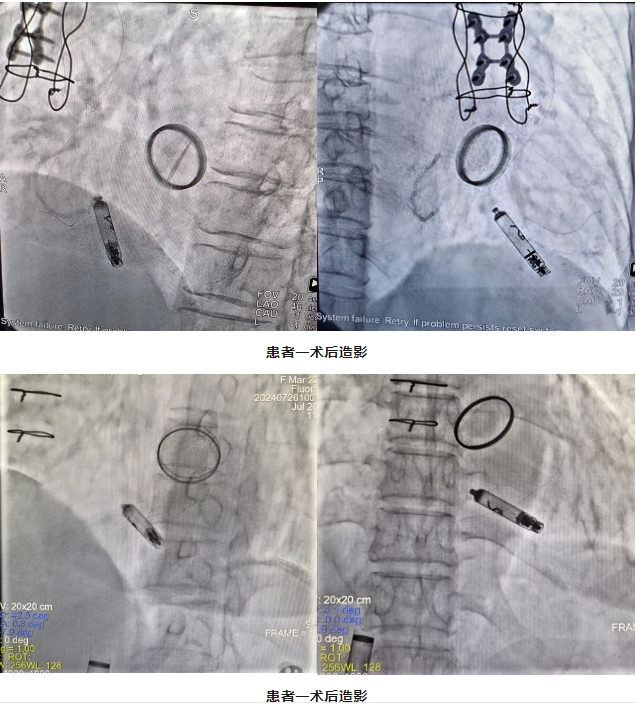

近日,江西省人民医院-省心血管病医院刘元庆团队在省心血管病医院院长赖珩莉主任医师的指导下,成功为两名心律失常患者植入了首批Aveir无导线心脏起搏器。江西省人民医院成为全国首批开展此项新技术的医院,为患者带来了前所未有的安全、便捷的治疗体验,更在行业内树立了新的标杆。

患者一为老年女性,75岁,12天前无明显诱因出现心慌,伴头晕、胸闷不适,既往曾行三尖瓣成形术、二尖瓣机械版置换术,全面检查后被诊断为房颤伴间歇性三度房室传导阻滞。

患者二为老年女性,60岁,因病态窦房结综合征被收住入院,完善全面检查后被诊断为阵发性心房颤动伴长R-R间歇、病态窦房结综合征、风湿性心脏病、风湿性三尖瓣关闭不全、甲状腺功能减退症、频发性房性期前收缩、阵发性房性心动过速、阵发性室性心动过速。既往行二尖瓣机械瓣置换术、三尖瓣成形术。

两位患者均为高龄,身体基础较差,病情复杂,长期服用华法林抗凝药物,为避免囊带血肿及感染风险,提高患者生活质量,经过科室讨论、综合评估其治疗方案及患者治疗意愿,最终决定为两位患者植入Aveir无导线心脏起搏器。